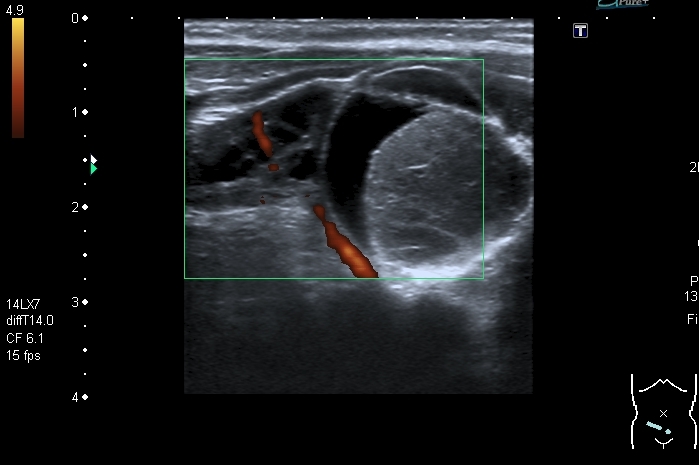

У девочки 5 месяцев ранее на УЗИ нашли образование в полости таза . С заключением киста яичника направлена к нам.

На УЗИ справа от мочевого пузыря - солидно - кистозное образование около 3 см. Образование прилежит к правому яичнику, который визуально не изменён, но смещается относительно его при движениях брюшной стенки Относительно яичника образование гиповаскулярное Выставил диагноз объёмного образования полости таза (дифференцировать энтерокистому и дермоид). Не думаю, что образование исходит из яичника, поэтому стартую тему в гастроэнтерологических исследованиях.